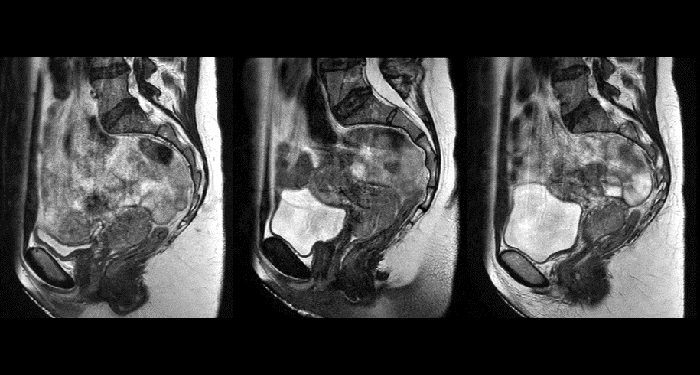

With its exceptional soft-tissue visualization capabilities and wide range of image contrasts, MRI has become a powerful tool to help more precisely define tumor boundaries. This is particularly important as it has been established that there is a high degree of uncertainty in target volume delineation, and it is even reported to represent the largest uncertainty in the entire radiotherapy process for most tumor sites**. Better visualization of the target area and nearby organs-at-risk is a key factor in enhancing target volume delineation. MRI’s expanding role also can be attributed to its functional imaging capabilities, which can inform both target characterization and treatment response.

With its superior soft tissue contrast compared to CT, MRI offers exquisite visualization of tumor boundaries and proximity to nearby critical structures.

In addition to anatomical imaging, MRI offers the ability to obtain functional information that is beneficial for tumor detection and delineation, and for response monitoring.

Diffusion-weighted imaging (DWI) for example depicts areas of high signal intensity in soft tissues that are indicative of the restricted water mobility (i.e., diffusion) of a tumor and can also be used to identify lymph nodes. Changes in the tissue’s or lesion’s apparent diffusion coefficient (ADC) can provide insights that help predict the tumor’s response to radiotherapy.